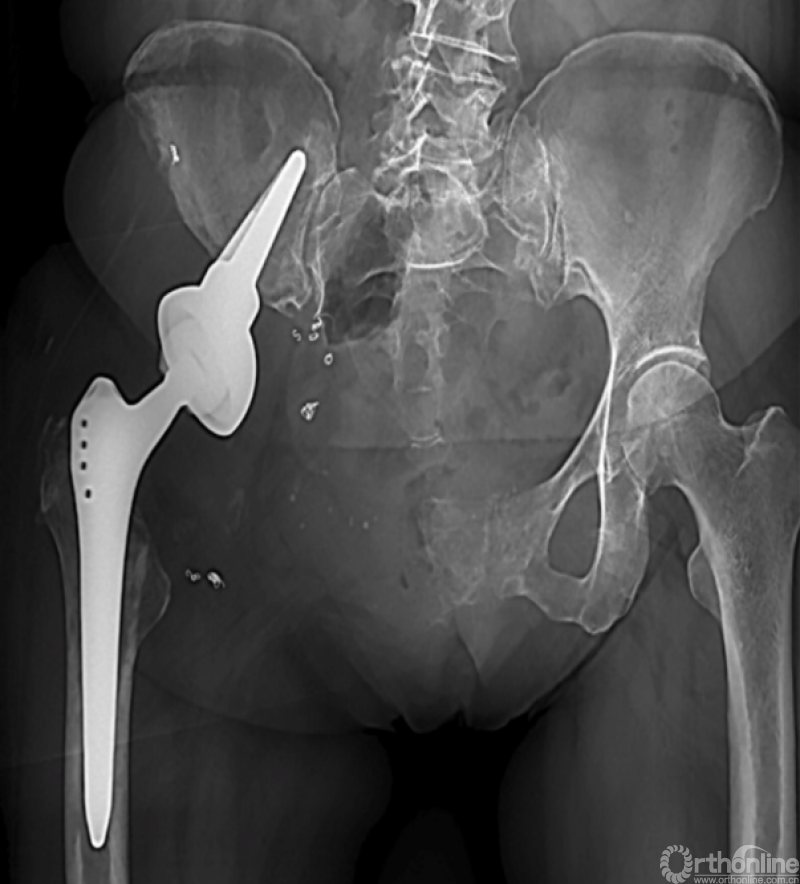

马鞍式假体未与宿主骨形成稳定的骨性连接,整体功能较差,并且并发症发生率较高[2-5](图1)。冰激凌假体与宿主骨的连接更加紧密,但不适合骨盆I区大部分切除的骨缺损,不能重建完整骨盆环[6-10](图2)。组配式半骨盆假体组装灵活,且可进行骨盆环完整重建,但其安装技术要求高,假体组件间存在断裂风险,不匹配得假体与宿主骨锚定将直接影响骨整合,最终易导致松动[1,11-15](图3)。

图2 冰激凌假体